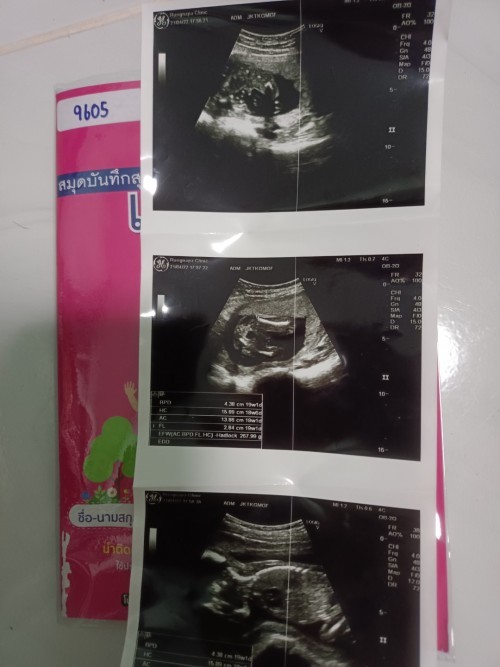

บ้านนี้ ธนวาจ้าลูกสาว

Post reply image